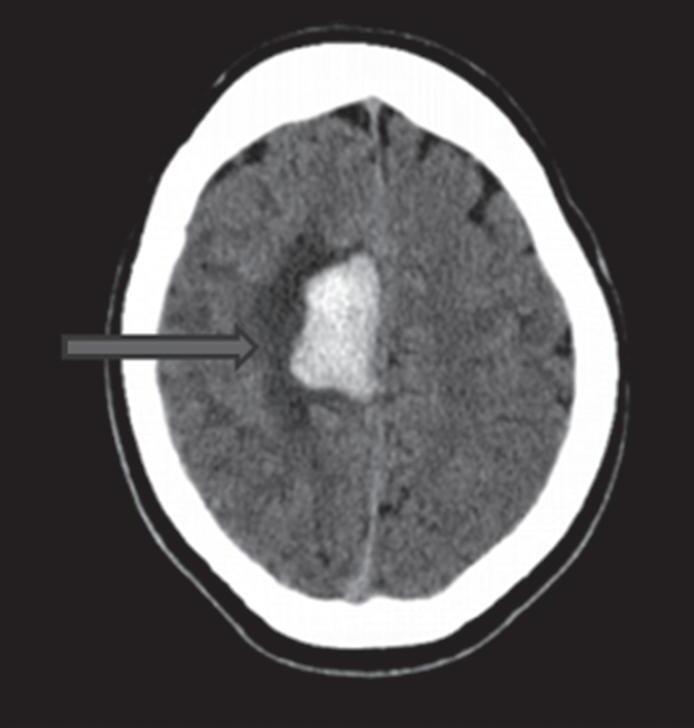

Com relação à apresentação clínica, as MAVs podem ser classificadas em dois grandes grupos: rotas e não rotas, como representado nas Figuras 1-5 a 1-7. As MAVs não rotas subdividem-se em dois subgrupos: sintomáticas e assintomáticas, sendo a crise convulsiva o sintoma mais comum nas MAVs não rotas; embora a importância das crises epilépticas seja muitas vezes negligenciada em favor da hemorragia intracraniana, que é o evento mais frequente e temido da história natural das MAVs. Em contrapartida, as crises epilépticas não devem ser deixadas em segundo plano porque podem ser debilitantes e comprometer a qualidade de vida do paciente.23,25

Outra classificação relacionada com a topografia divide as MAVs em: parenquimatosas, durais puras e mistas (durais e parenquimatosas). As parenquimatosas subdividem-se em: piais, subcorticais, paraventriculares (Fig. 1-10) e combinadas. Sendo que as piais, quando rompem, estão associadas mais frequentemente à hemorragia subaracnóidea e as paraventriculares associam-se ao hemoventrículo associado ou não à hidrocefalia obstrutiva.26